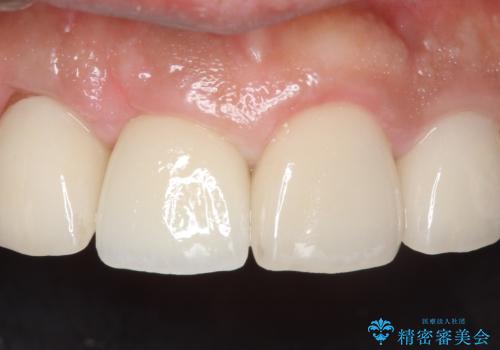

- 右上の前歯が土台ごと外れたといらっしゃった方の症例です。

ファイバーコアという土台から建て直し、咬み合わせに十分注意した上で、オールセラミッククラウンによる補綴を行いました

今回用いたオールセラミッククラウンはジルコニアフレームという白い素材の上にセラミックを盛っているため、審美性が非常に高いのが特徴です。